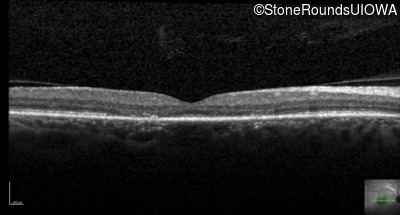

Optical Coherence Tomography - Left - 20/20 sc

Exemplar / OCT Stack